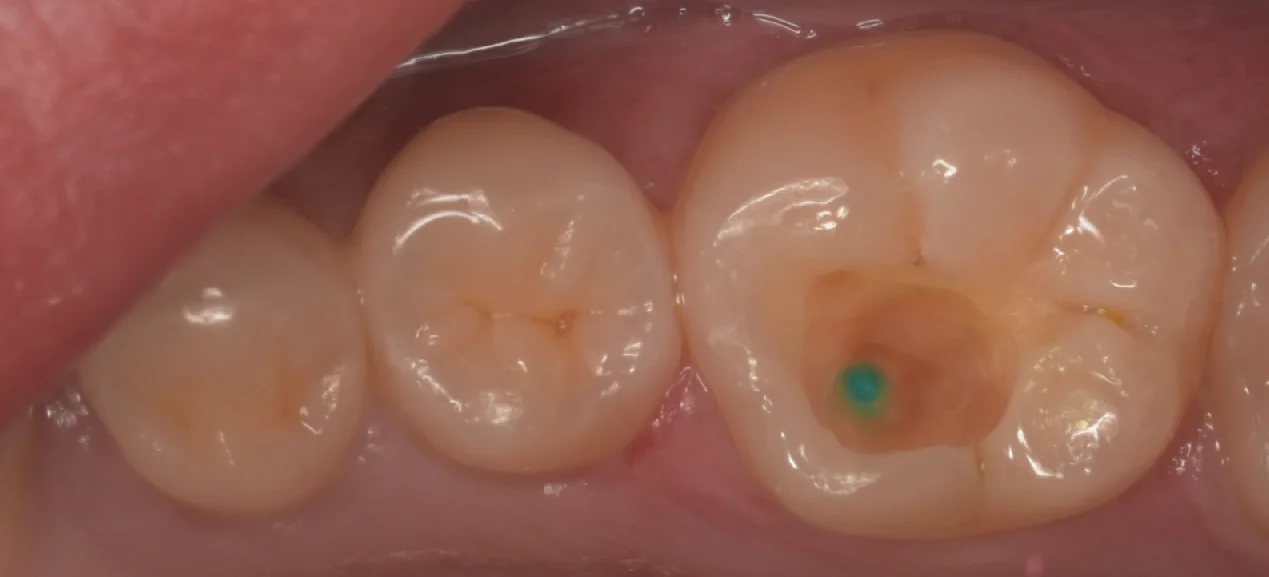

そして充填後の写真がこちらです。

溝の部分の色も手前の歯に調和させるようにしたので、違和感もあまりなく詰められたかと思います。

斜めからの写真がこちら。

ちょっとレンズに汚れがついていたのか黒い点が写ってしまっていますね(⌒-⌒; )

ちなみに術前術後の写真がこちらになります。

随分違和感なく仕上げられたとは思います。

本人も非常に喜んでいただけました。